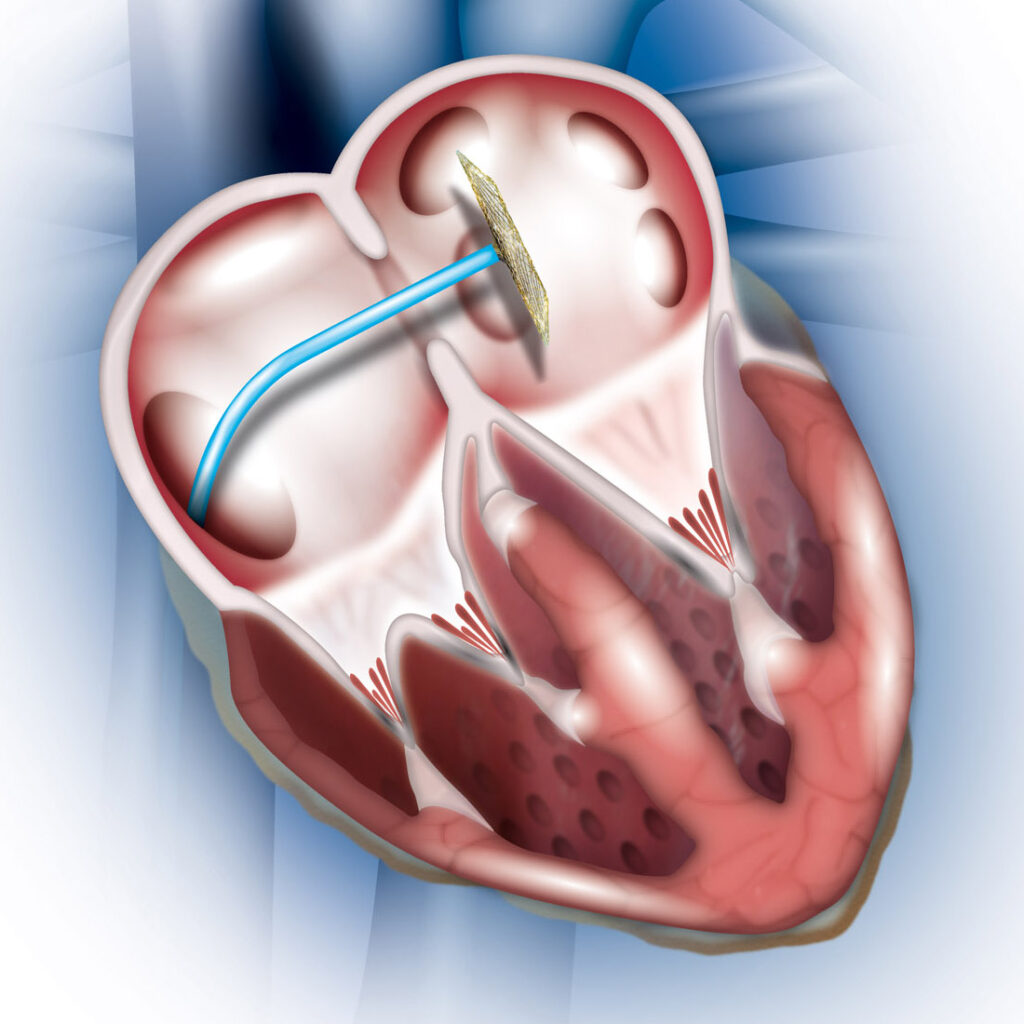

بستن PFO با اینترونشن

بستن سوراخ بیضی قلب PFO با استفاده از اینترونشن

بستن سوراخ ASD با اینترونشن